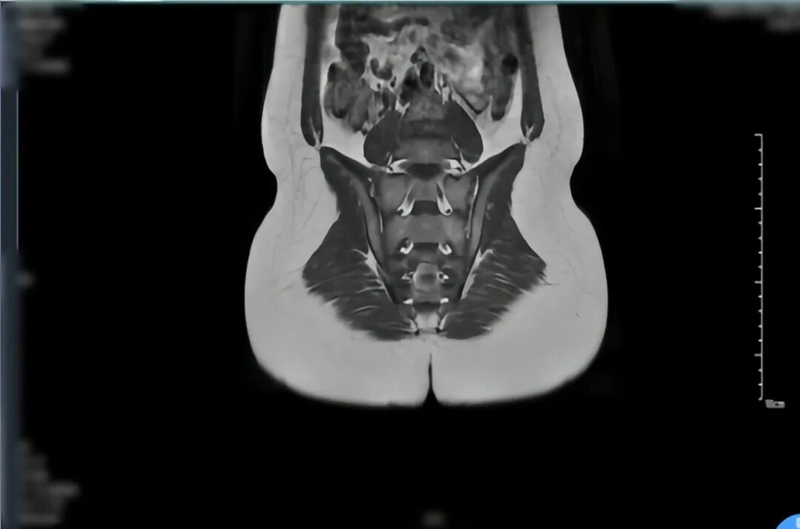

检查结果显示,小轩的血沉、C-反应蛋白等炎症指标明显升高,HLA-B27 筛查呈阳性(该指标与脊柱关节病密切相关,对诊断有重要参考价值);右足磁共振检查发现距骨、跟骨存在“骨髓水肿”,骶髂关节影像也显示关节面有骨髓水肿和炎症迹象。

经过一段时间的调理,小轩的状态越来越好,近期复查关节 MRI 显示炎症明显改善,终于摆脱了疼痛的阴影,重新回到了绿茵场。